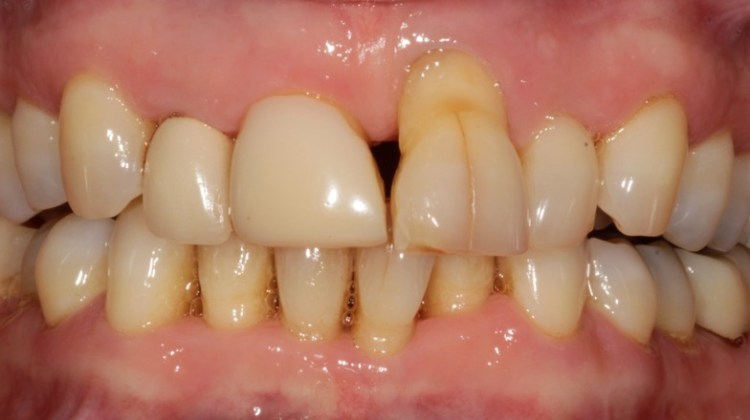

Crowns may be used to treat toothwear or broken down teeth. They are often selected where composite has failed, the teeth are too broken down or there is a need to provide a stronger material. This case was managed with surgical crown lengthening and multiple crowns. The lower incisors were treated with composite.